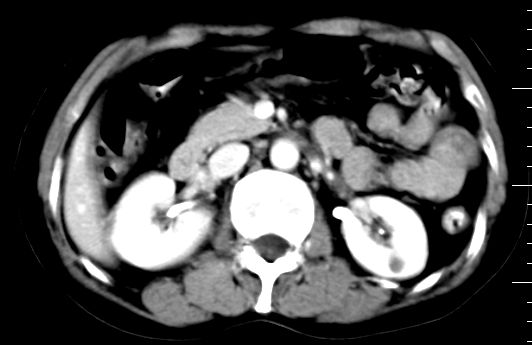

标题: CT10752:F,52岁,反复上腹部疼痛,平扫+增强. [打印本页]

f、52岁,反复上腹部疼痛2年。肺结核病史10多年,胸片双上肺结核纤维化。

ct表现:

肝大小形态未见异常,肝内外胆管无扩张,肝s8段见一动脉期明显血管样强化结节,门脉期呈高密度,延迟期呈等密度,胆囊不大,增强扫描见胆囊及胆囊颈管壁增厚,有强化。

双肾灌注良好,代谢增快,动脉期肾盂见造影剂,左肾下极背侧见一略低密度病灶,延迟期见似不强化囊肿,双侧肾上腺未见异常。

胰腺及脾未见异常。肾门水平腹膜后见小淋巴结。腹腔未见积液征象。

诊断:

1、胆囊炎(轻度)。

2、肝s8段结节,考虑小血管瘤。

3、左肾下极低密度灶,考虑囊肿可能性大,建议随访,除外小肾癌(无强化可以基本除外)。

4、目前ct表现尚不能解释患者上腹部疼痛,建议上消造影检查,除外胃炎等疾患。